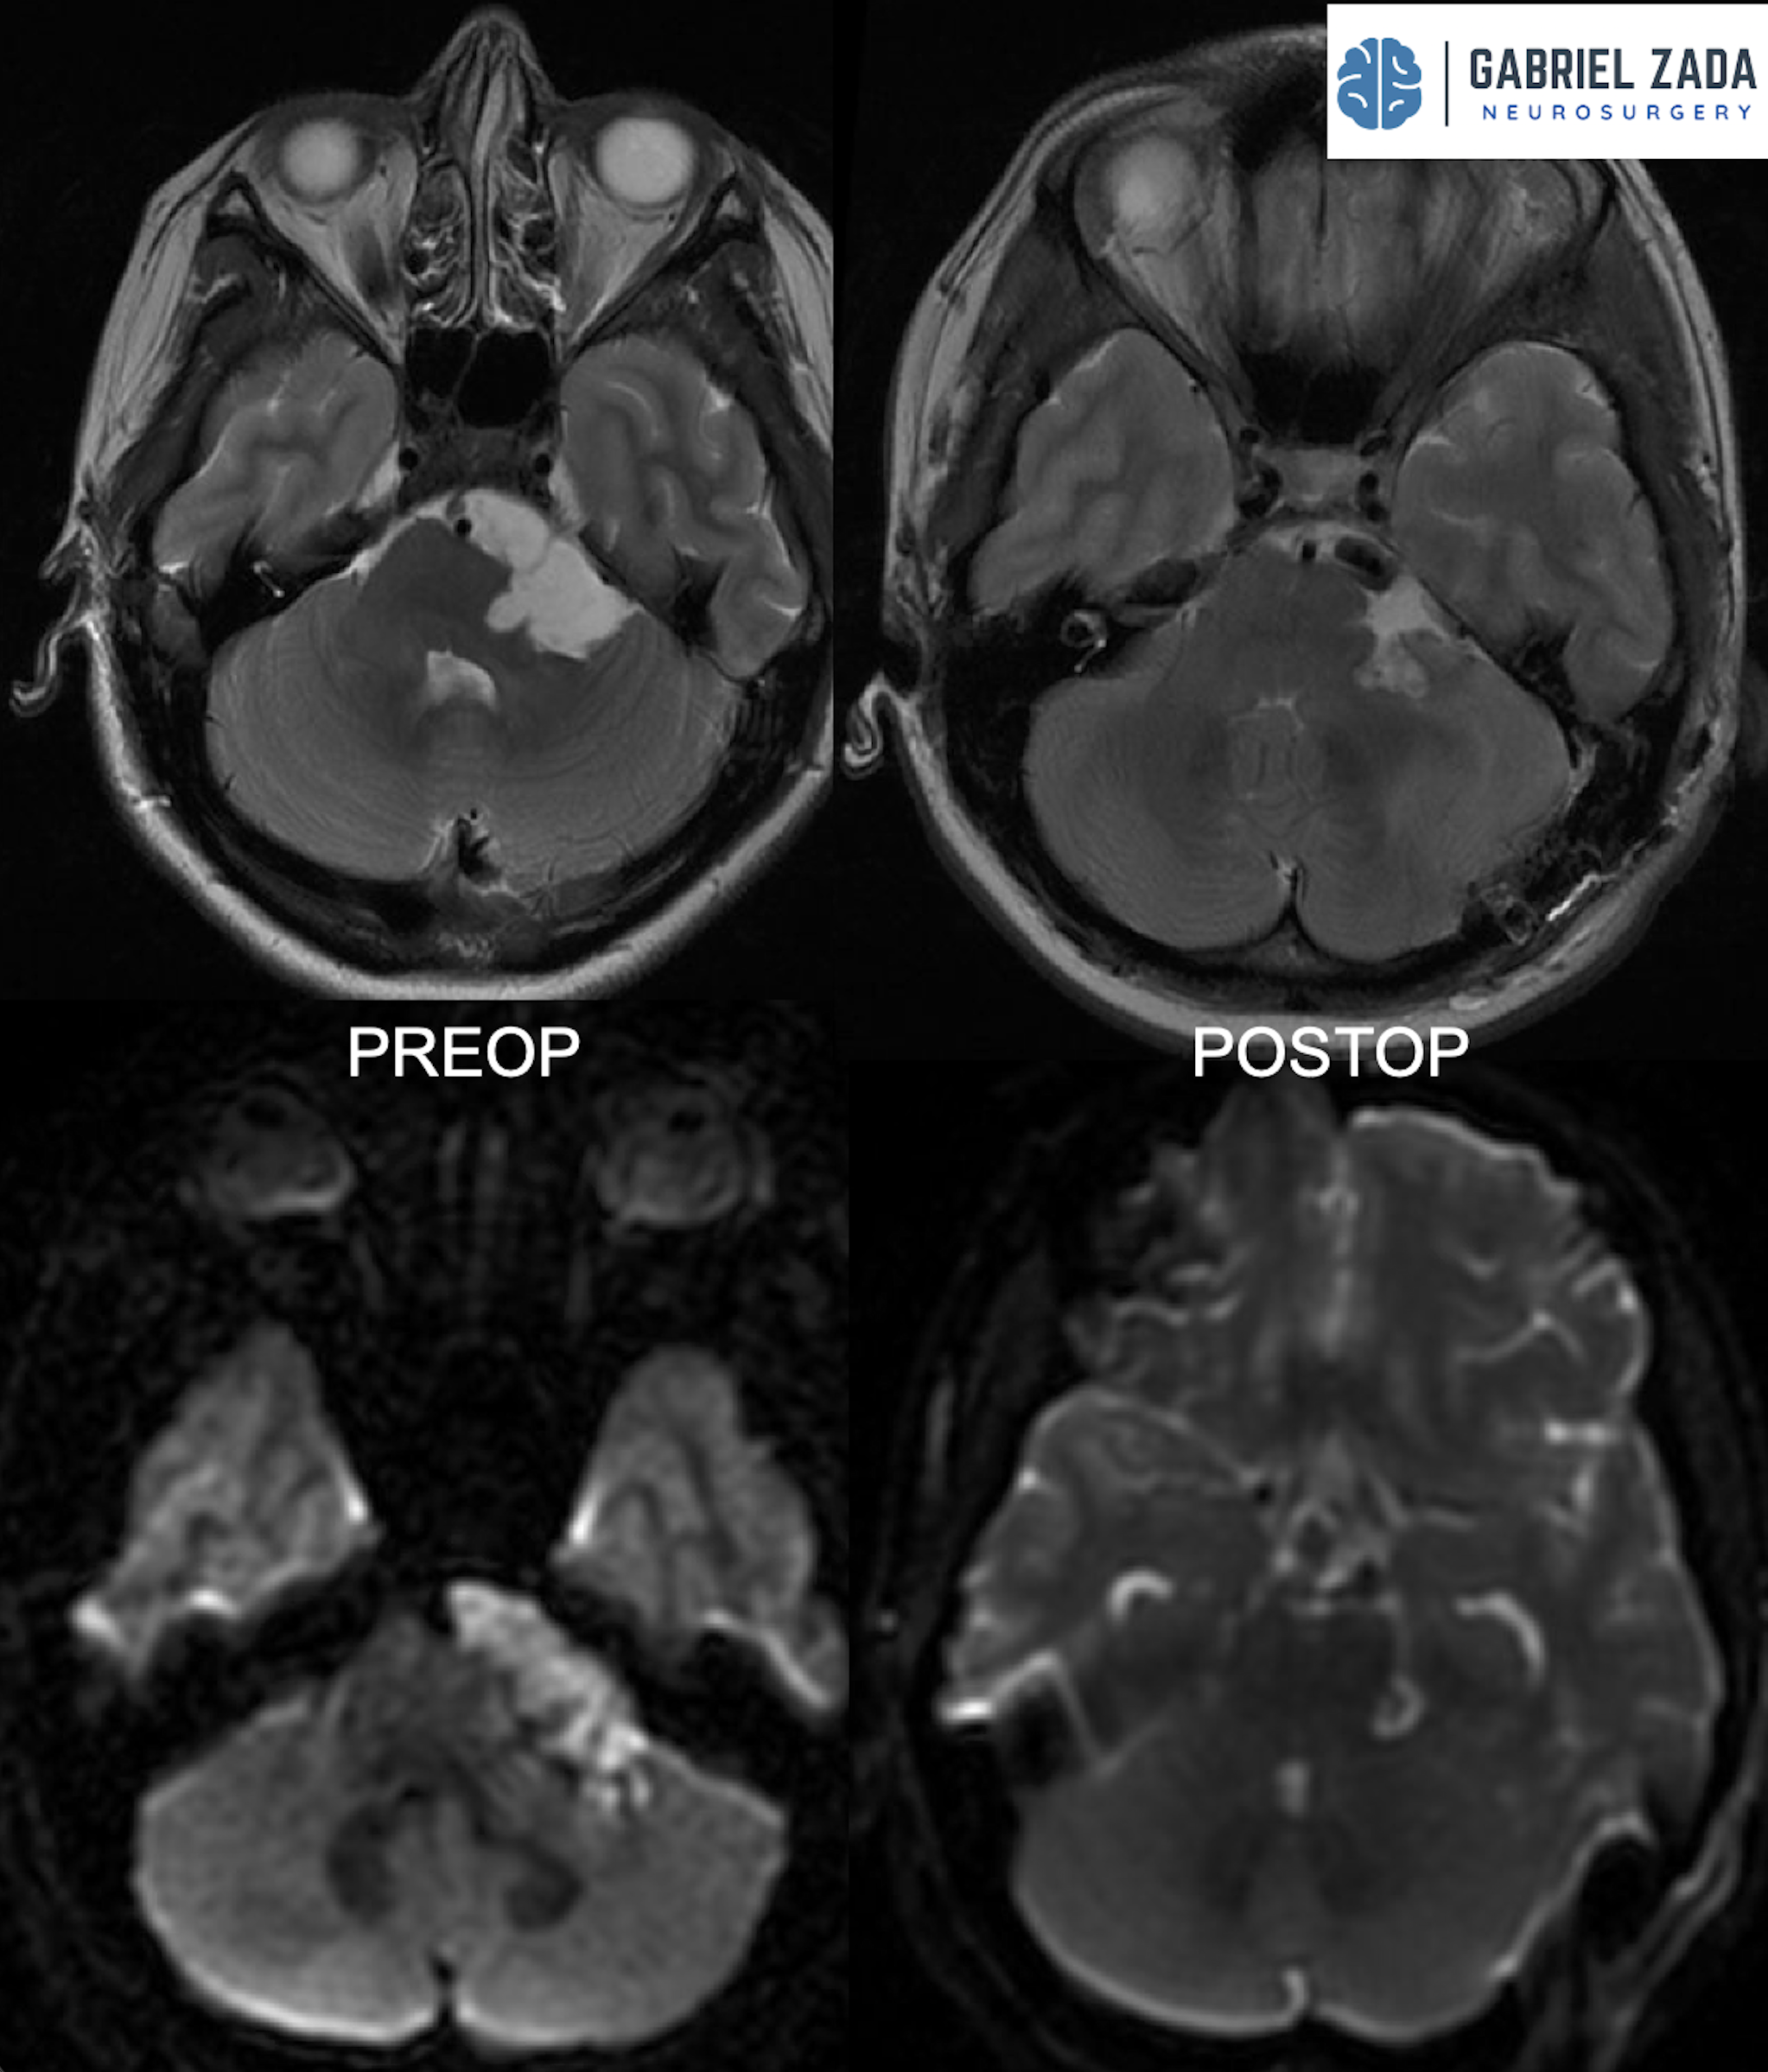

Explore this comprehensive gallery featuring pre‑ and post‑operative imaging of patients with skull‑base tumors treated by Gabriel Zada, MD, MS, FAANS, FACS. These cases highlight Dr. Zada’s expertise in advanced neurosurgical techniques and outcomes.

*Representative cases shown for educational purposes. All images de-identified. Individual results vary.